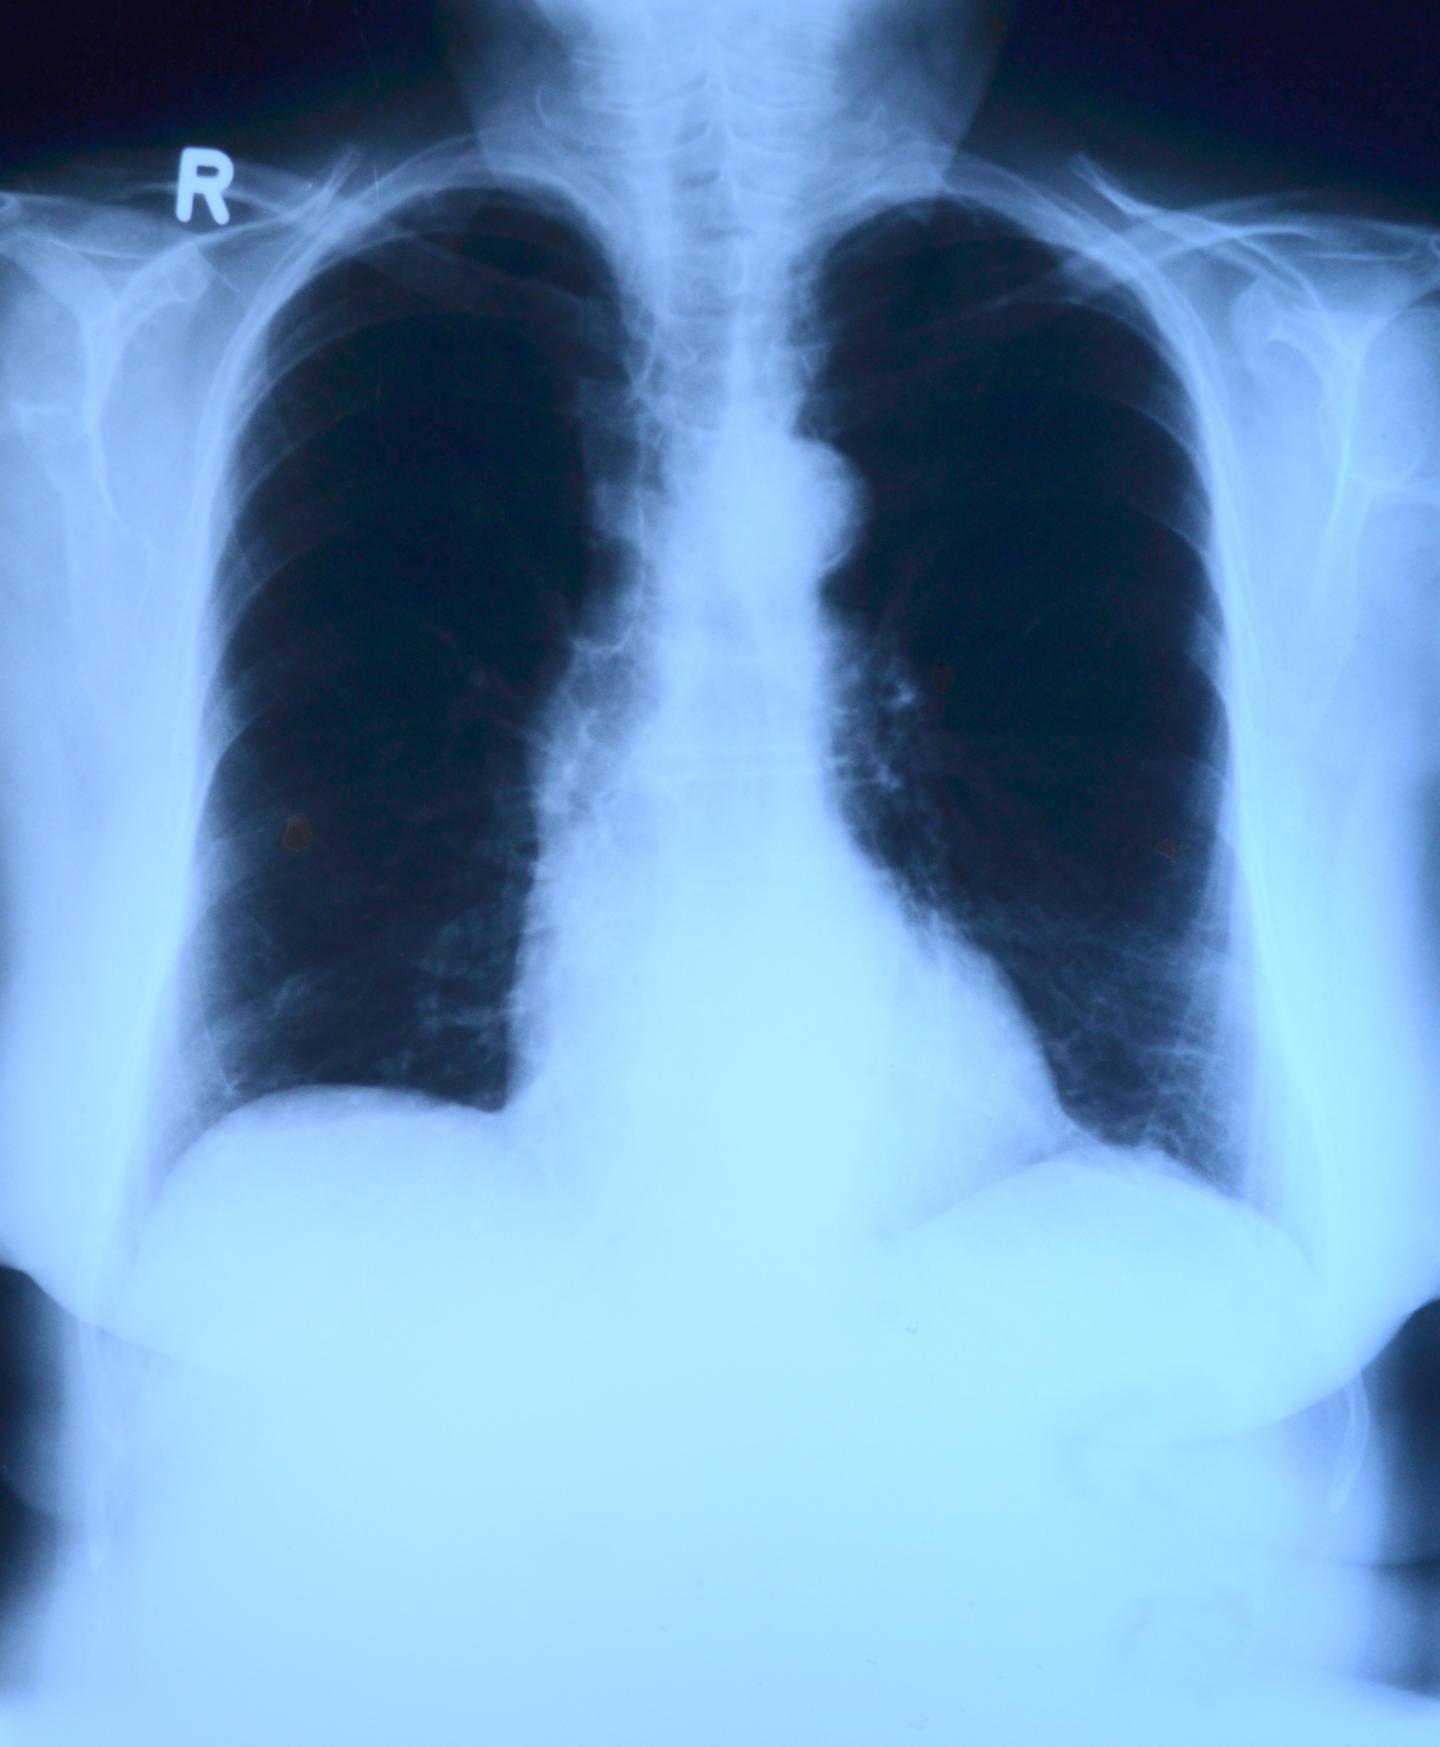

chest xray film of the patient with pneumonia right lower lung. Covid Chest X Ray Cost For Covid When patients are encouraged to present early in. 17 however, with respect to the relative value of chest radiography or ct for detecting the presence of viral pneumonia, the experience is vastly different depending on community norms and public health directives. This rapid advice guide examines the evidence and makes recommendations for the use of chest imaging in acute care. Chest X Ray Cost For Covid.